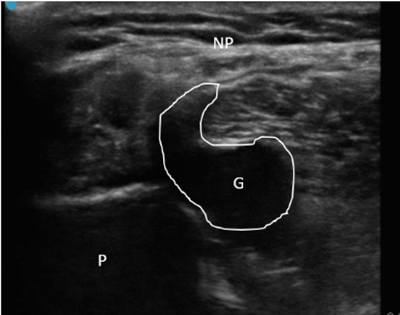

Neuropatía peronea secundaria a ganglión extraneural: revisión de literatura y propuesta de tratamiento. Caso no positivo

Peroneal neuropathy caused by an extraneural ganglion: literary review and treatment proposal. A non-positive case

Este artículo presenta el caso de un paciente de 69 años con una neuropatía compresiva peronea secundaria a un ganglión, inicialmente interpretada como una radiculopatía L5. Este incorrecto enfoque supuso la sobremedicación del paciente, un mal control algésico, la realización de una discectomía L4-L5 innecesaria y una pobre evolución neurológica.

Un enfoque diagnóstico correcto y un abordaje terapéutico precoz habrían supuesto una mayor mejoría clínica e incluso una recuperación neurológica completa del paciente. Por ello, este caso sirve para resaltar: a) el valor de la ecografía en neuropatías periféricas como herramienta diagnóstica y pronóstica y el de la ecografía en gangliones como arma diagnóstico-terapéutica; b) el uso de las pruebas diagnósticas como apoyo a una exploración física exhaustiva, y no como diagnóstico en sí mismas, y c) la importancia de la publicación de casos no positivos para optimizar recursos, evitar repetir errores, reducir el sesgo de publicación y facilitar el inicio de proyectos de investigación.

Figura 2